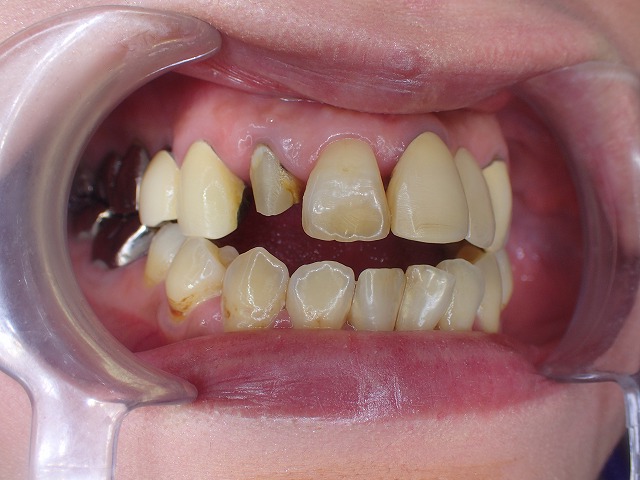

差し歯が折れた場合、単に被せ直せば済むとは限りません。

この症例では、土台にネジ(スクリューピン)が使われており、内部に強い感染と歯根の亀裂が見つかりました。

この記事では、差し歯が折れた歯の内部で何が起きていたのか、そしてどのように治療を進めたのかを症例ベースでご紹介します。

このページの結論

差し歯が折れた場合、見えている部分だけでなく、

内部の土台や歯根の状態まで確認することが重要です。

この症例では、スクリューピンが使われた土台の周囲で不適合や破損が起こり、

強い感染と歯根の亀裂がみられました。

そのため、単なる被せ直しではなく、根管治療・ファイバーコア・

最終的な被せ物の再検討が必要になりました。

今回は費用面などを考量して、健康保険で制作できる

cad/cam冠を選択しました。

見ての通り、歯根に亀裂が入っています。